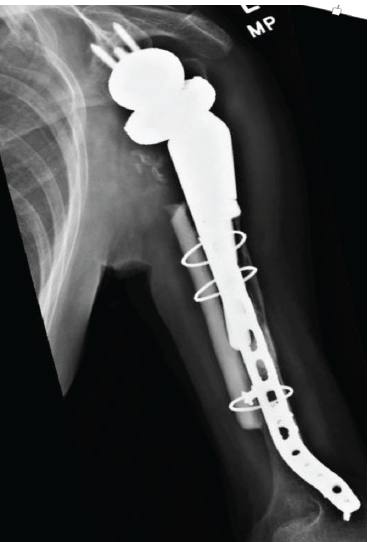

The second stage of the revision was performed 4 months after the antibiotic spacer was placed. Tissue at the time of the revision surgery revealed no white blood cells per high-powered field, so further reconstruction was performed with a custom tumor prosthesis (Comprehensive Segmental Revision System; Zimmer Biomet), which was cemented in the humeral shaft (Fig. 4).

Figure 4: Anteroposterior radiograph showing second stage of revision of reverse total shoulder arthroplasty with removal of the spacer and implantation of a tumor prosthesis.

At 4 months after surgery, the patient fell in an elevator shaft in her home from a height of 1.2 m, landing on the operative arm. She sustained a fracture distal to the tip of the prosthesis (Fig. 5). She subsequently underwent open reduction and internal fixation with a plate and a fibular allograft for support.

Figure 5: Lateral radiograph of the humerus showing diaphyseal fracture distal to the tip of the prosthesis.